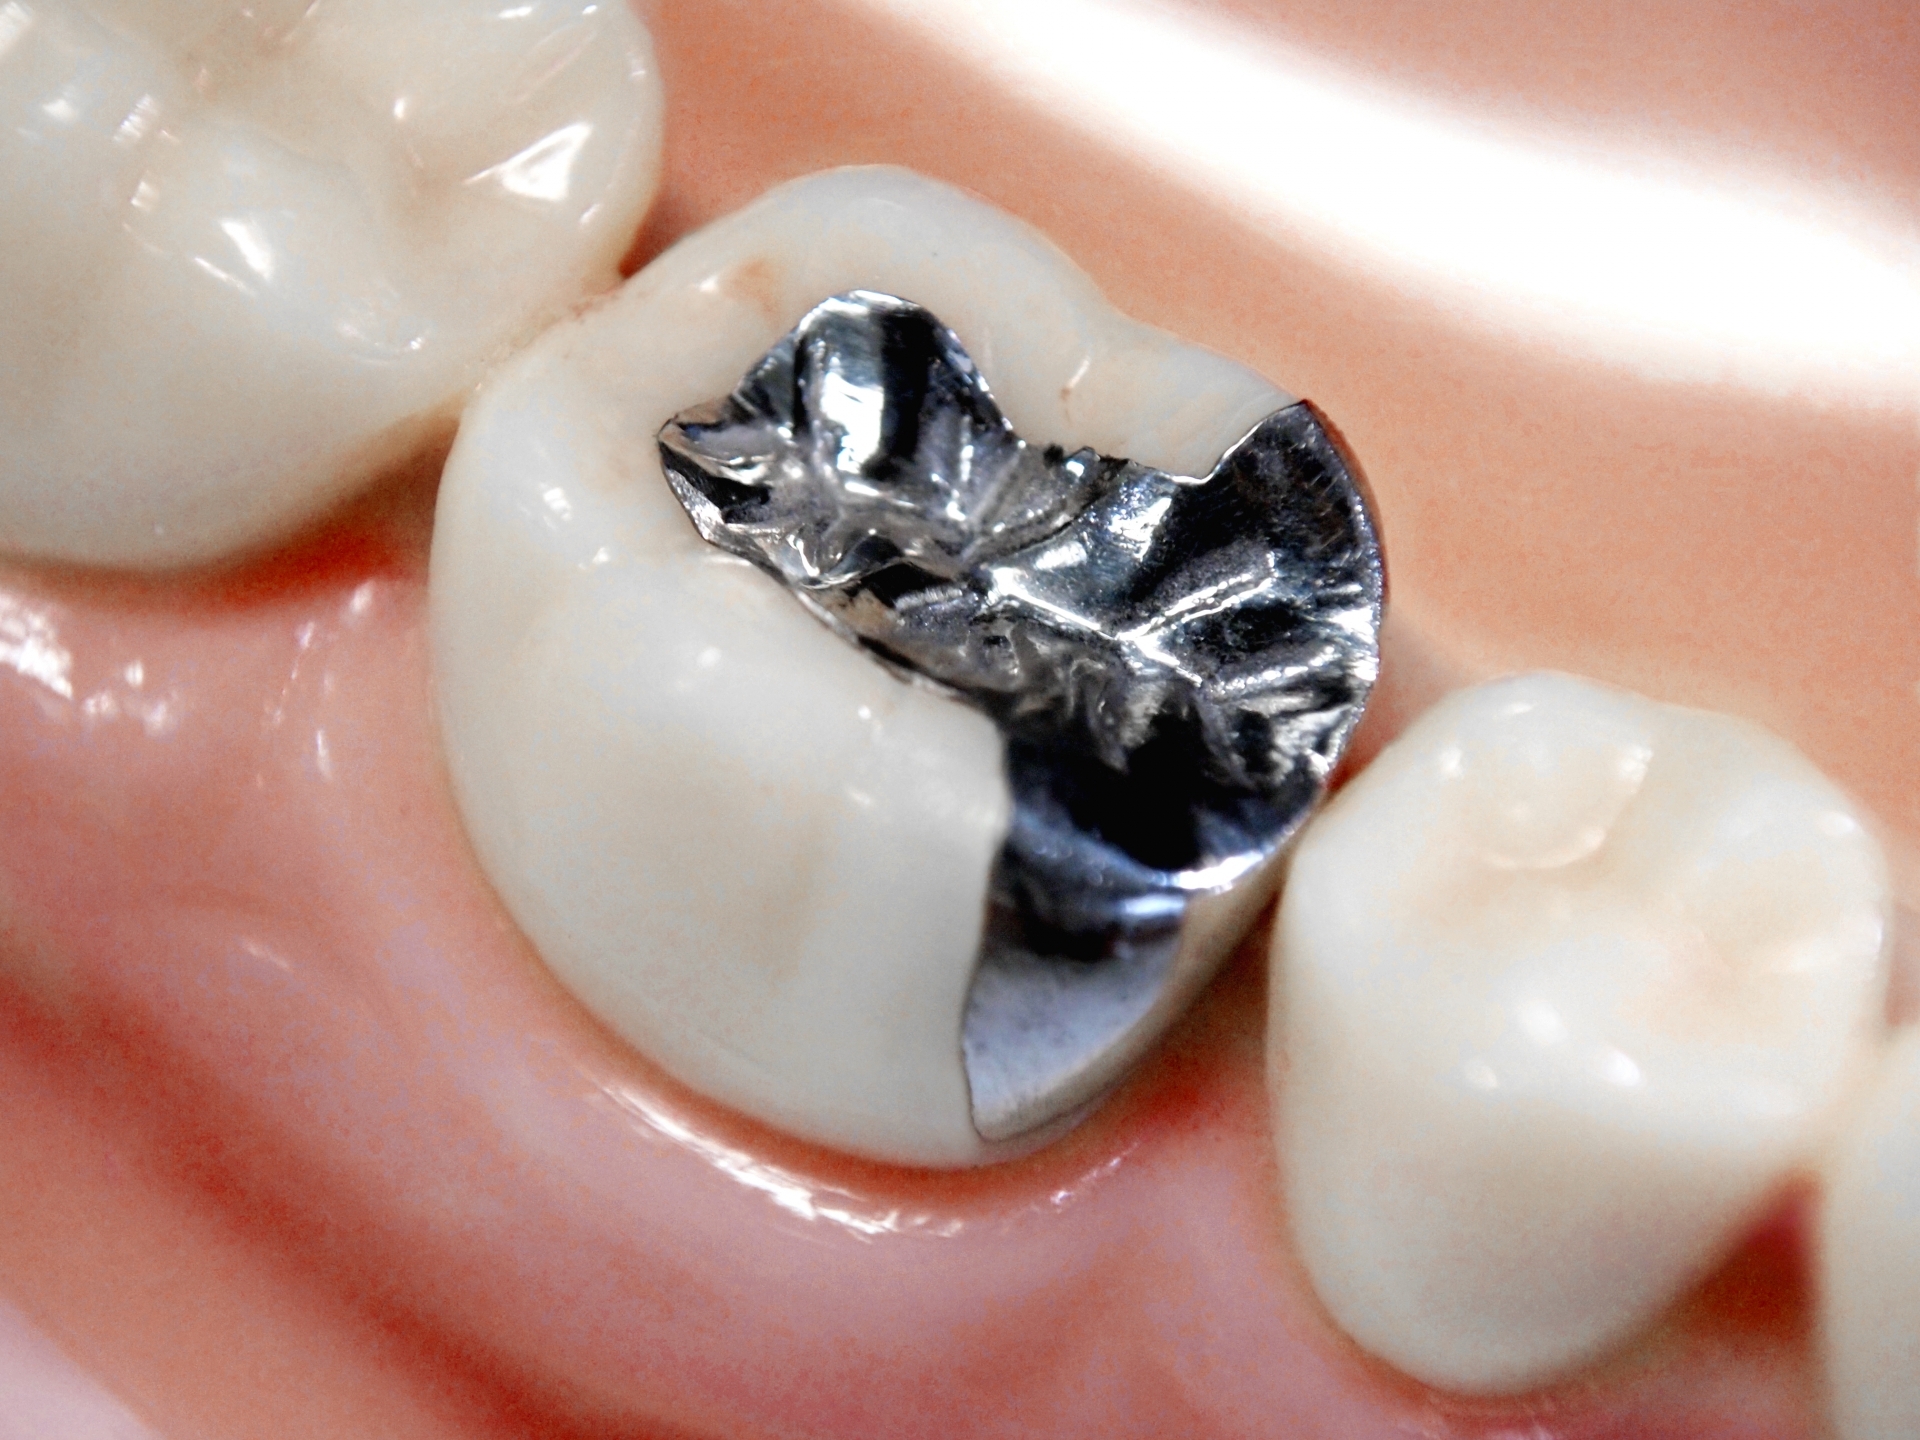

治療前の説明をしっかり行い、虫歯の治療、予防、歯科矯正、義歯の治療、ホワイトニングなど患者さまそれぞれのニーズに合わせた最新の治療の提供を心がけています。 お口の中の悩みがある方はぜひ一度小松歯科医院に足をお運びください。